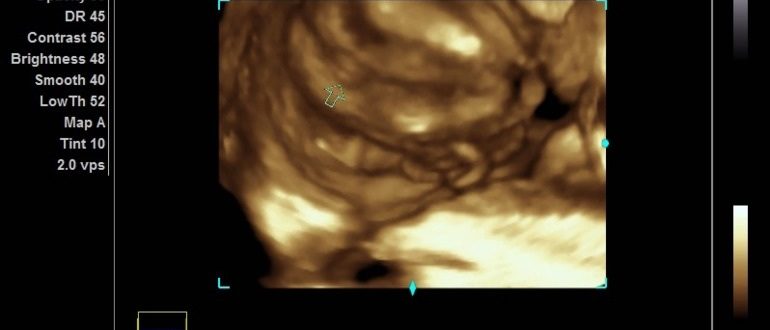

Почему на УЗИ один врач видит то, чего не видит другой? Ультразвуковое исследование помогает безболезненно проверить почти все органы. Но при проведении УЗИ врачи иногда ошибаются и пугают сомнительными диагнозами….